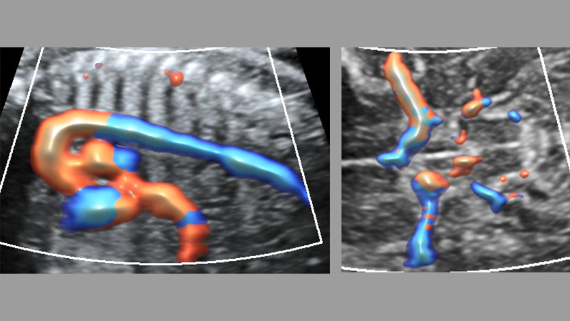

Obrazy kliniczne